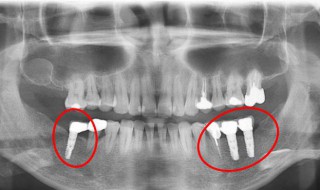

1、给牙齿打桩,是指在牙齿缺损较大,或因为外伤等原因只剩下牙根时,因剩下的牙齿过短或力量过于薄弱,不能用修复体(主要指烤瓷牙)直接修复,需要给牙根里打桩,加固并延长折断的牙齿,以使假牙能获得足够的力量固定。

(1)由于龋坏(虫牙),外伤等原因造成牙冠大面积缺损者;

(2)牙齿缺损只剩下牙根,牙根还可以利用残根(已经没有牙冠)根面达牙龈下,牙周健康,牙根有足够的长度,经牙龈切除术能暴露出根面者;